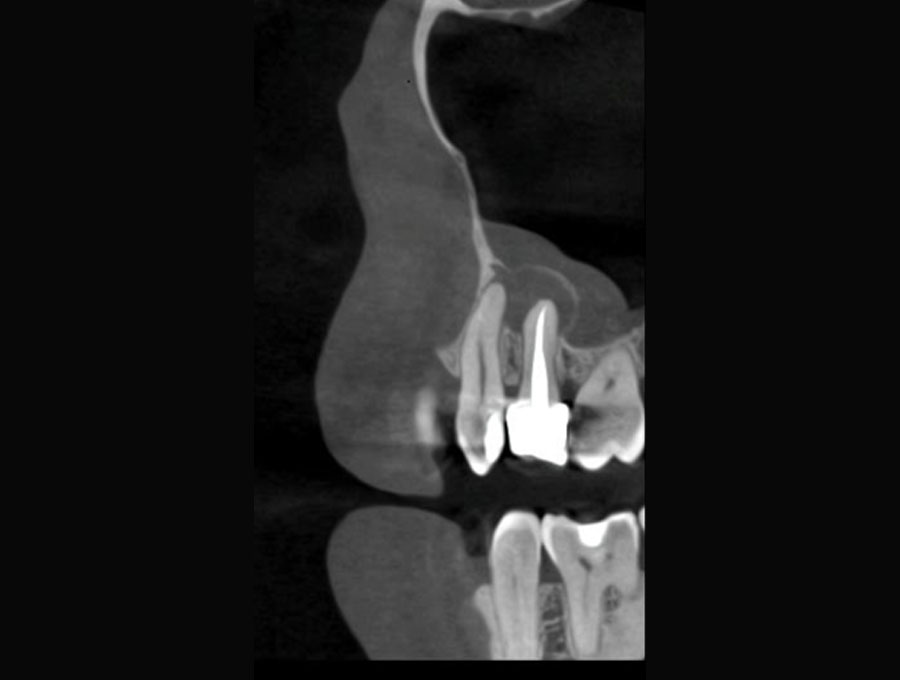

Σήμερα, στο «οπλοστάσιό» μας, έχει προστεθεί και η υπολογιστική τομογραφία κωνικής δέσμης (CBCT), οι εικόνες της οποίας είναι ιδανικές τόσο για να μας πληροφορήσουν για τη μορφολογία του συστήματος των ριζικών σωλήνων αλλά κυρίως να μας βοηθήσουν στη διάγνωση των βλαβών στο άκρο της ρίζας, στην έκταση αυτών των βλαβών και τη σχέση τους με παρακείμενες ανατομικές δομές (π.χ. ιγμόρειο).

Ατελής ενδοδοντική θεραπεία που οδήγησε σε περιακρορριζική καταστροφή.

Η επανάληψη της ενδοδοντικής θεραπείας δεν οδήγησε σε πλήρη επούλωση της βλάβης,

καθώς είναι αναγκαία και η περιοδοντική θεραπεία του δοντιού.

Χρόνια φλεγμονώδης περιακρορριζική βλάβη, κυρίως,

λόγω ενδοδοντικής αιτιολογίας. Μετά την ενδοδοντική θεραπεία

ακολούθησε περιοδοντική θεραπεία.

Δύο χρόνια μετά, παρατηρείται πλήρης εξαφάνιση της βλάβης.